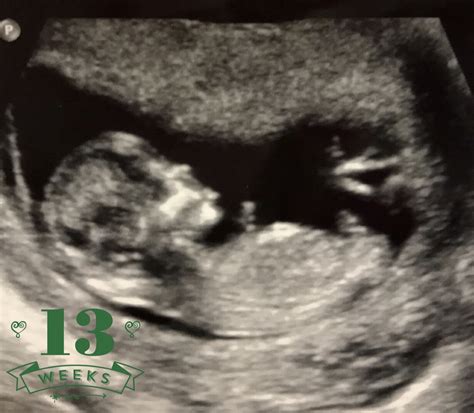

13 Weeks Ultrasound

Pregnancy is an exciting journey filled with milestones, and one of the most anticipated moments is the 13 Weeks Ultrasound. This scan, typically performed between 12 and 13 weeks of gestation, offers a wealth of information about the developing fetus and the mother's health. Understanding what to expect during this ultrasound can help alleviate anxiety and prepare expectant parents for the next steps in their pregnancy journey.

A 13 Weeks Ultrasound is a routine prenatal check-up that uses high-frequency sound waves to create images of the fetus and the uterus. This scan is crucial for several reasons, including assessing the fetus's development, detecting any potential issues, and providing a clearer picture of the pregnancy timeline.

• Visual Confirmation: Seeing the fetus on the ultrasound screen can be an emotional and reassuring experience. At this stage, the fetus is about the size of a plum, and its features are becoming more distinct.